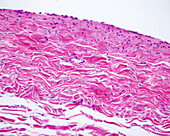

13613516 - Vein adventitia, light micrograph